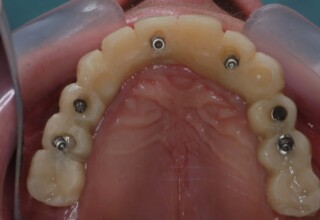

Ολική Στοματική Αποκατάσταση σε Εμφυτεύματα με διαφορετική προσέγγιση στην Άνω και Κάτω Γνάθο

Κάτω γνάθος: εξαγωγές, άμεση τοποθέτηση εμφυτευμάτων και άμεση φόρτιση(την ίδια ημέρα) με προσωρινή γέφυρα

Άνω γνάθος: σταδιακές εξαγωγές, σταδιακή τοποθέτηση εμφυτευμάτων και σταδιακή ενσωμάτωση τους στην προσωρινή γέφυρα ώστε η ασθενής να μην μείνει ούτε μια ημέρα χωρίς αποκατάσταση. Στόχος η συνεχής λειτουργική και αισθητική αποκατάσταση της ασθενούς χωρίς άμεση φόρτιση των εμφυτευμάτων λόγω ανατομικών ιδιαιτεροτήτων.

Χρησιμοποιήθηκαν παλαιές χαμογελαστές φωτογραφίες της ασθενούς γιατί είχε χαθεί τελείως το φυσικό σχήμα των δοντιών εξαιτίας των πολλαπλών προσθετικών προσπαθειών που είχαν γίνει στο παρελθόν. Μεταφέρθηκε στην προσωρινή γέφυρα η σχέση των φυσικών δοντιών μεταξύ τους άλλα και με τα χείλη. Δοκιμάστηκε η φώνηση και η μάσηση με δυο διαφορετικές προσωρινές άνω γέφυρες και εκτιμήθηκε η αισθητική απόδοση τους. Αφού επιτεύχθηκαν σε βαθμό ικανοποιητικό η φώνηση και η αισθητική εμφάνιση της οδοντοφυΐας, η προσωρινή αποκατάσταση χρησιμοποιήθηκε ως οδηγός για την τελική.